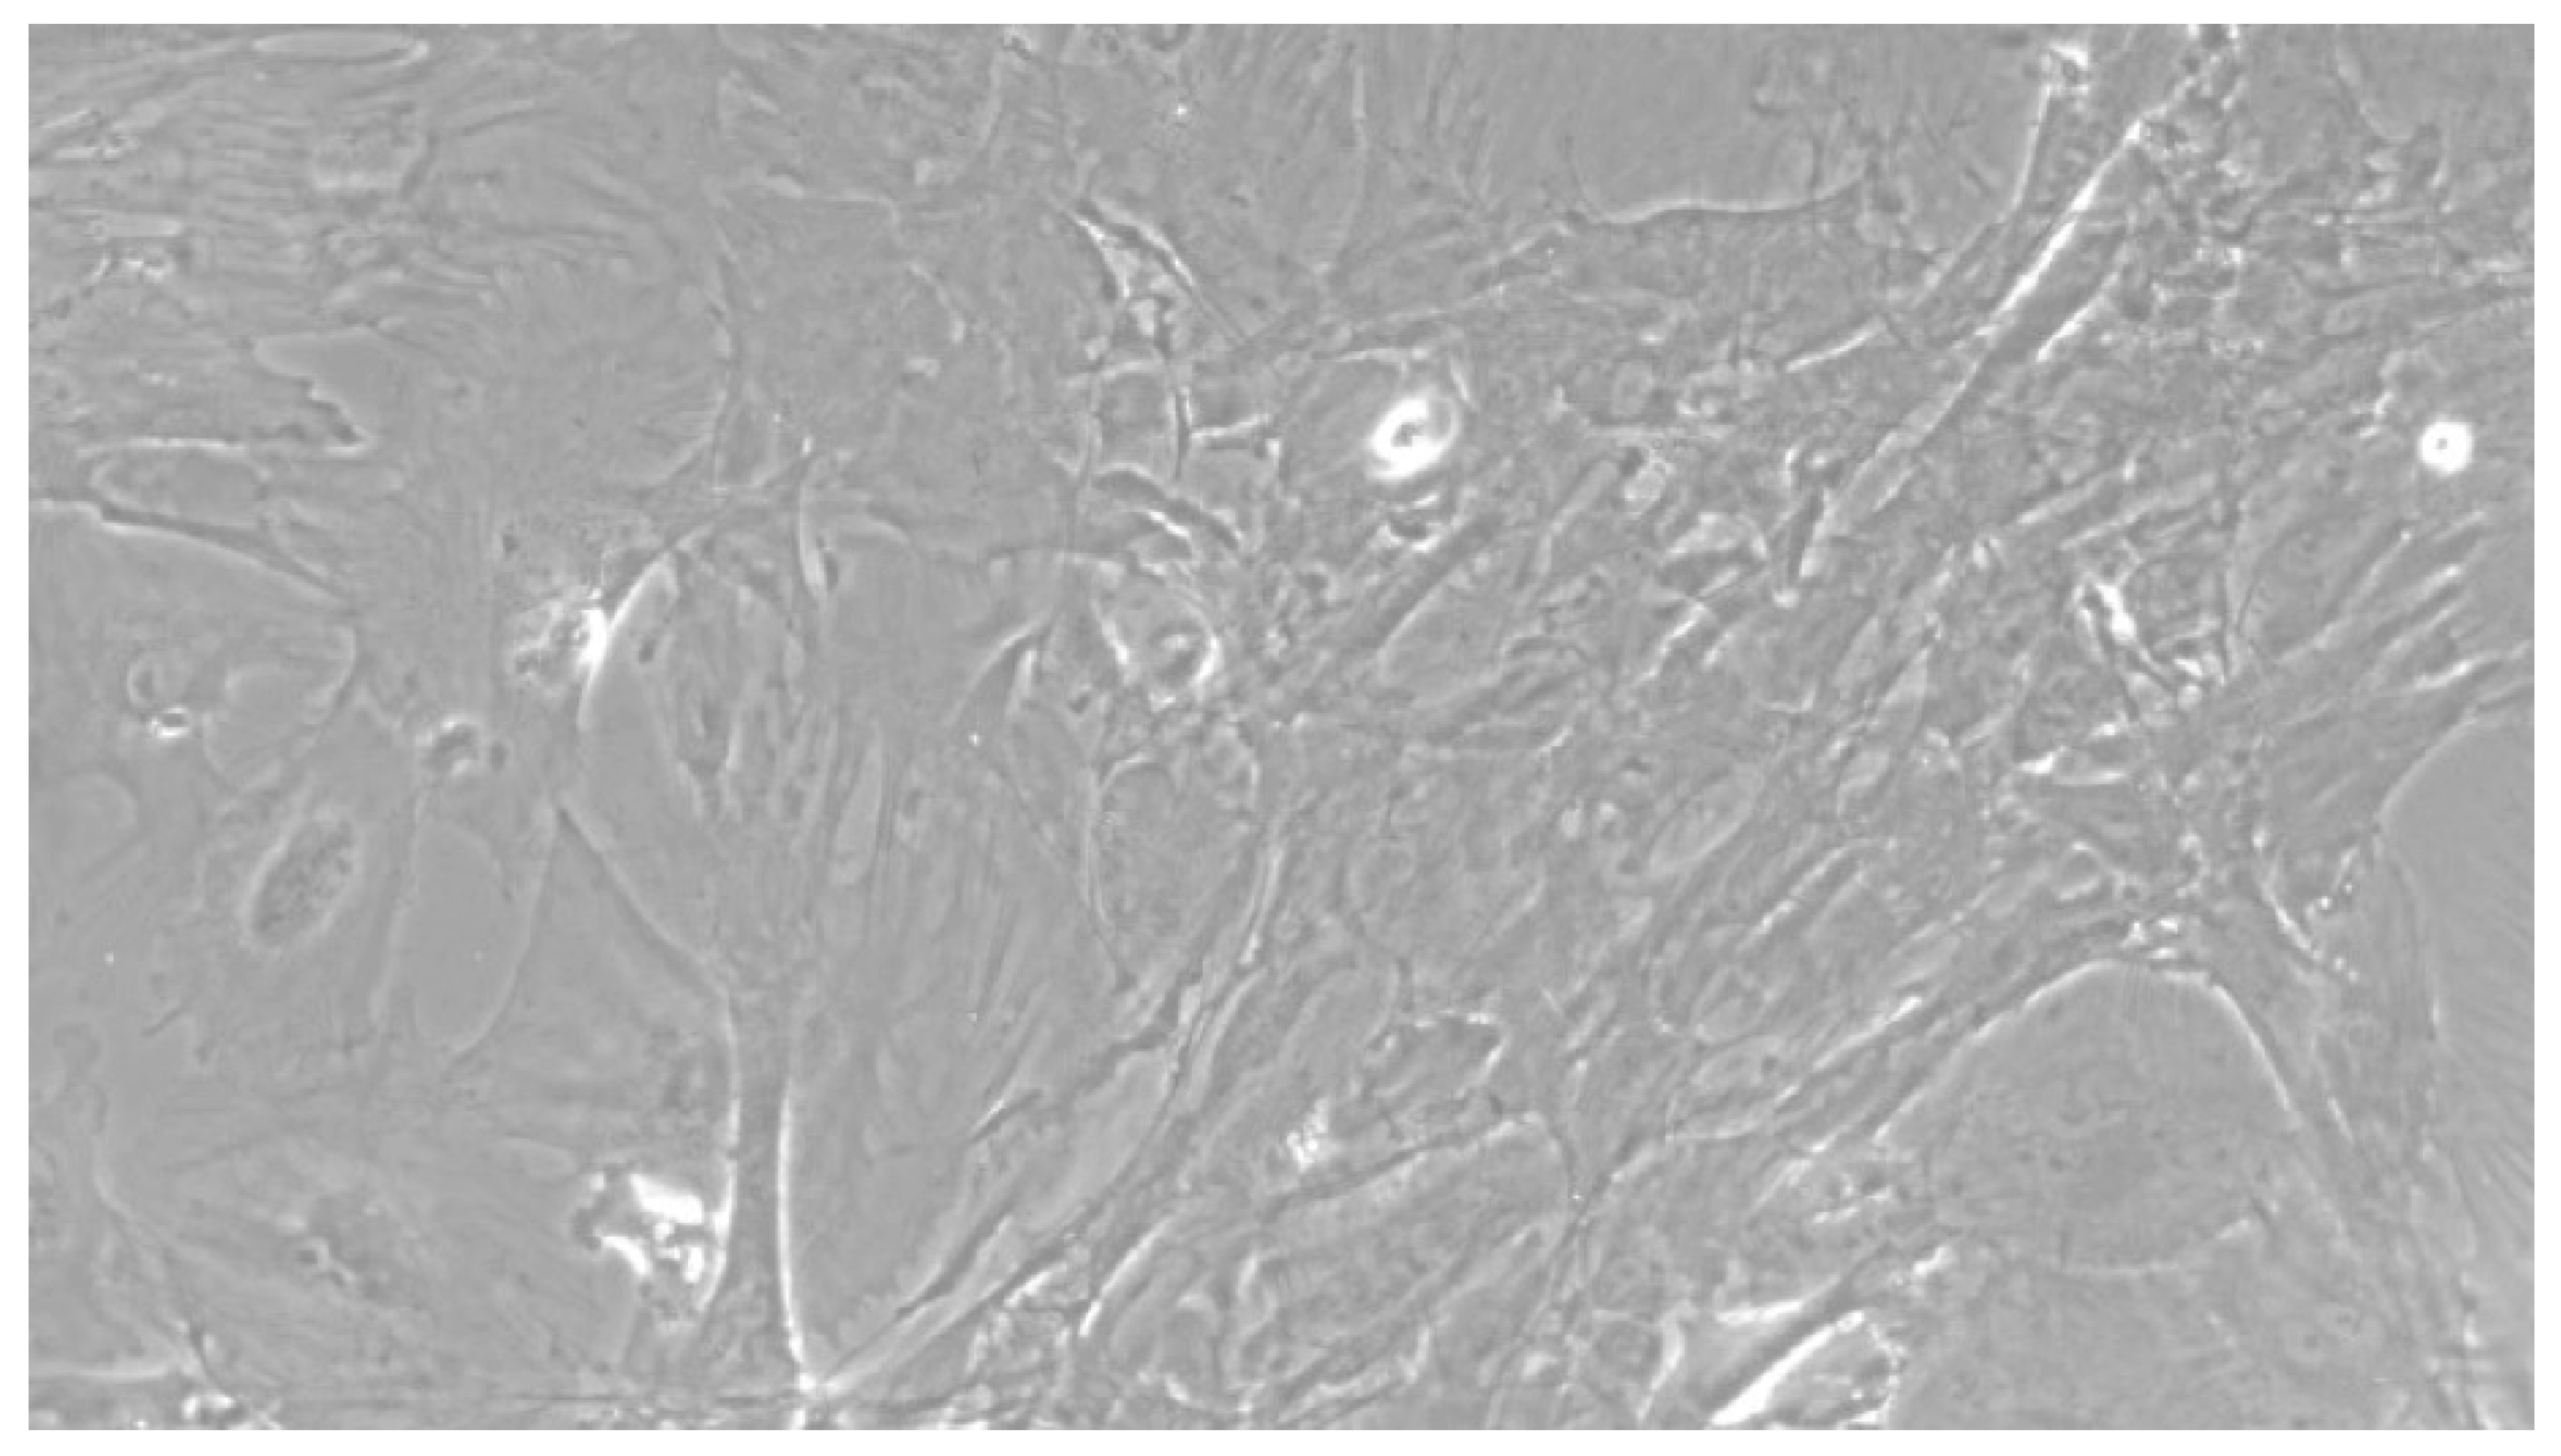

Figure 2.

Once the EBs were ready they were plated in an osteogenic differentiating medium that allowed them to mature into osteoblasts; we can see from the images how, from the first days, the cells showed the typical morphologies of osteoblasts. The 8+RA control (cell clone) in the osteogenic differentiation medium initially showed rapid growth, as seen from the optical microscope images. (magnification 20×–10×, plates 70,000 cells). We see clone growth at 1, 4 and 5 days.

Figure 3.

CTR8#14 P12 + retinoic acid showed a slower growth than the start of day 12 of differentiation. In the optical microscope image, in fact, we can see how the cells are organized in the typical osteoblast structure: concentric and tapered. (magnification 10×, plates 70,000 cells).